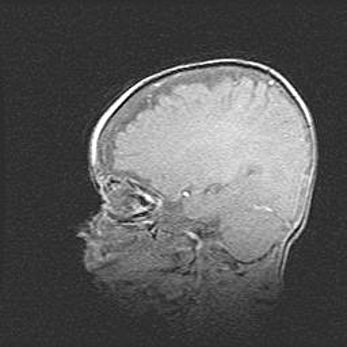

Неполная лизэнцефалия (пахигирия). Открытая гидроцефалия.

Возраст: 17 дней

Вес: 3110 г

Пол: мужской

Окружность головы: 33,5 см

Срок гестации: 35-36 недель

Лизэнцефалия—недоразвитие корковой пластинки и мозговых извилин в результате нарушения миграции нейронов коры. Поверхность мозговых полушарий гладкая. Микроскопически выявляется отсутствие нормальных слоев коры и скопление групп нейронов в подкорковом белом веществе.

Пахигирия—уменьшение числа вторичных извилин. В пораженном полушарии нервные клетки образуют толстый недифференцированный слой с неправильно расположенными нервными волокнами и группами гетеротопных клеток. Нервные клетки незрелые. Белое вещество истончено. При этом нередко аномально развит корково-спинномозговой путь.